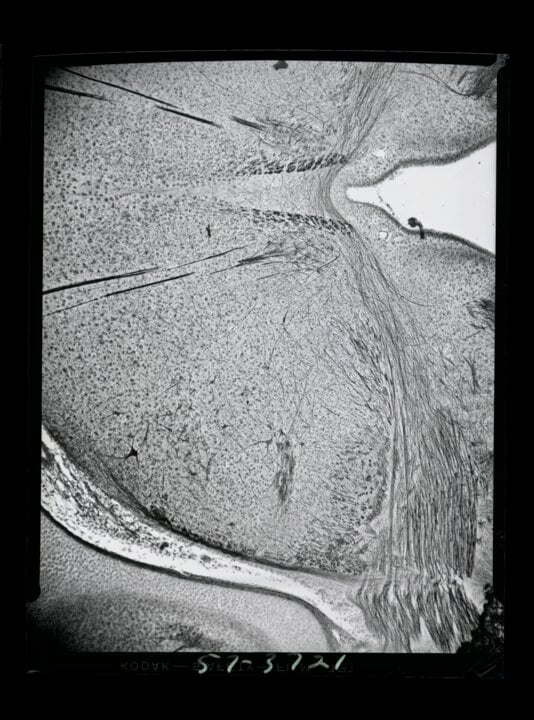

2 (of 2) Image four in a photomicroscopy series of chick embryo cerebellum and optical cortex development, dating from May 1957. These images document some of Levi-Montalcini's work studying the generation of chick optic nerves.

Photo: © Becker Medical Library, Washington University School of Medicine

2 (of 2) Image three in a photomicroscopy series of chick embryo cerebellum and optical cortex development, dating from May 1957. These images document some of Levi-Montalcini's work studying the generation of chick optic nerves.

© Becker Medical Library, Washington University School of Medicine